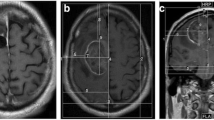

EMBC 2019 also included a talk by Wenger et al. [26], discussing the use of water content-based electric property tomography (wEPT) in order to create patient models for TTFields-related numerical simulations. wEPT is an imaging tomography technique that models electrical conductivity, σ, and relative permittivity, ε, as monotonic functions of water content (WC) according to Maxwell’s mixture theory [13]. WC maps are found via a transfer function mapping the image ratio (IR) of two T1w images with different repetition times (TR) into water content. Previously, wEPT was adapted to map WC, σ, and ε at 200 kHz in animal brain samples and tumor-bearing rats with mixed results [26]. When comparing wEPT-based predictions to empirical measurements of tissue samples using a parallel plate setup, we found a good match between wEPT-based estimations in the healthy tissue, while the quality of the match was poor within the tumors. At EMBC 2019, data were presented on the applicability of wEPT to mapping the electric properties of the human brain. The images used for wEPT mappings included, for this purpose, an image with a short TR resembling a conventional T1w MRI and a proton density (PD) image with the same parameters except for a long TR (Fig. 5).

(top-left) The tetrahedral mesh a of glioblastoma patient used to calculate TTFields induced electric field distributions, along with the (top row) distribution of conductivity for (top middle) a model created by segmenting a T1c image and assigning conductivity values to each tissue type and (top right) a model created using wEPT. Bottom row shows the field distribution in the (bottom middle) model created through segmentation and in the (bottom right) model created with wEPT. The flow chart in the bottom-left corner shows the wEPT scheme. First an image ration (IR) is calculated from the T1w and PD images. Next, WC is found from the IR, and conductivity derived from the WC. Note the parameters in the equations are found using curve-fitting to empirical data as detailed in Wenger et al. [26]

EP maps for three patients who participated in the EF-14 trial were created using wEPT. The adapted wEPT model coefficients were found via curve fitting according to previous experiments and MRI scanner-specific parameters. Analysis of the results showed that wEPT estimates of WC, σ, and ε in healthy brain tissues (white and gray matter) appear accurate and comparable with reports in literature. The properties were also relatively homogenous throughout the tissues and did not vary much between patients. Contrary, wEPT estimates of σ and ε in tumor tissues (necrosis, enhancing and non-enhancing tumor) were highly heterogeneous with high variability between patients.

These results, combined with results of our previous study, show the potential of wEPT-like methods for mapping the electric properties of the brain. However, the results suggest that wEPT alone is insufficient to map the electric properties of the tumor as well as the heterogeneous nature of the tumor. Future studies should focus on understanding the connection between tissue microstructure and the electric properties of the tissues at 200 kHz. When these processes are well understood, then methods for accurately mapping electric properties can be devised .